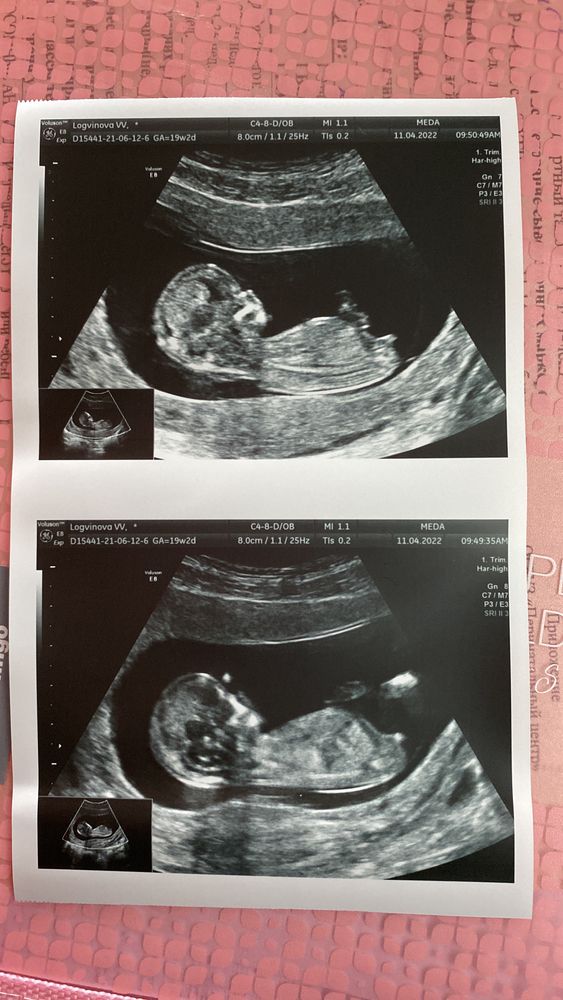

Сделали сегодня скрининг УЗИ + кровь, по первому УЗИ сегодня 12+1, а по скринингу теперь 12+4 - т.е пдр 20 октября и эТо замечательно 😀

А, да, посмотрите фотки - 100% же девочка 🤣 нафига я делала анализ крови и так все видно😂 прямо откровенно не мальчик

Smola, да нет по фото видно бугорок лежит - точно девочка))))

Smola, да на таком сроке только предположения - это он даже сказал)))) это я вижу что 100% девочка 😂 да я так уверена из-за теста наверное)